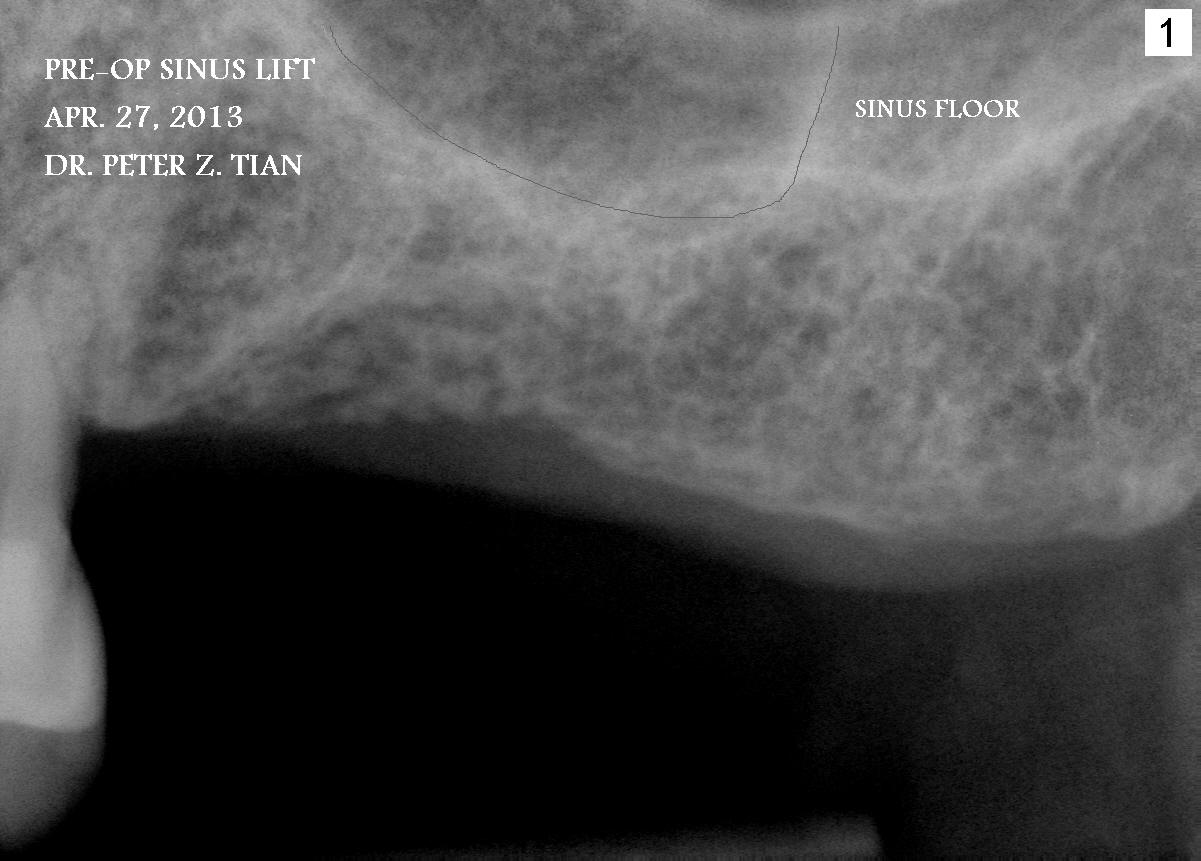

田氏上颌窦提高术

I just did the sinus lift with implant placement a few days ago. Drs. Wei and Mu are real experts. 班门弄斧了。Peter Tian Wednesday, May 1, 2013 10:11 PM

I used free hand drilling and I am very good about that. You need to training yourself. Basically, I need to watch the drill 3 angles, front, buccal and lingual to make sure they are parallel to #12 all the time.  I don't use commercial guide, it costs $$$.  I used little over 1g of bone. It took me about 1.5 h from sitting patient, to raise the flap, drill, lift, inject the bone, place implants, suture, give the instruction and collect the payment. No leaking, I used hydraulic sinus lift so that patient and I would know if there is any water leaking right away. Patient's son in law is ENT specialist. They know this very well.  Implants 4.8mm x 10mm, the bone thickness 7mm and 6mm. Peter Wednesday, May 1, 2013 10:36 PM